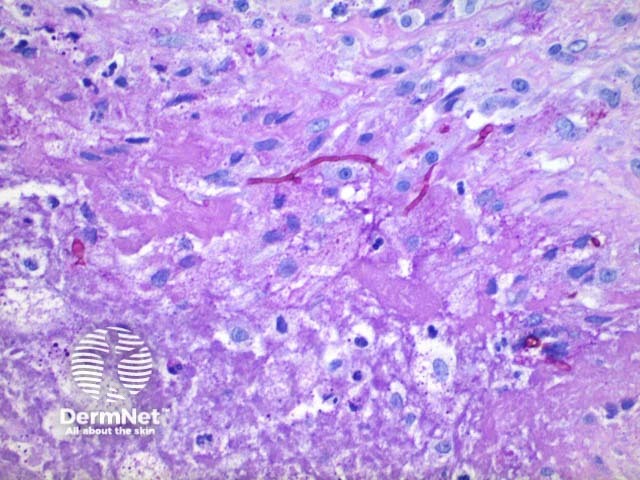

Scanning power view of phaeohyphomycosis shows a deeply extending granulomatous pattern (Figure 1) which may show areas of necrosis (Figure 2). Centrally an abscess or cystic nodule may form. Frequently a foreign body such as a wood splinter can be seen. The epidermis commonly shows pseudoepitheliomatous hyperplasia. The inflammatory infiltrate is comprised of histiocytes with multinucleated giant cells, and numerous neutrophils (Figures 3,4 and 5). At high power branching septate pigmented fungal hyphae can be seen (Figure 6).

Figure 5